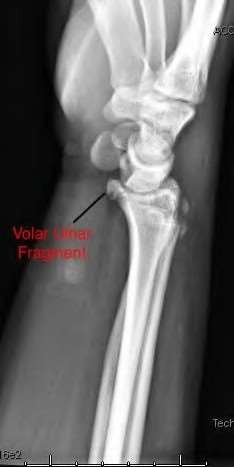

A 20-year-old park ranger trips and falls onto his right wrist with the wrist in extension and pronation. The local urgent care orders both radiographs and a CT, which you review and determine to be normal. The patient complains of ulnar-sided wrist pain. On exam, his tenderness is localized to the fovea. Ulnar deviation also causes him pain. There is no snapping sensation with wrist supination, flexion, and ulnar deviation. He otherwise has 5/5 strength to his first dorsal interosseous muscle with 4mm static two-point discrimination on the ulnar side of the 4th digit. Which of the following injuries is most likely responsible for his symptoms and exam?